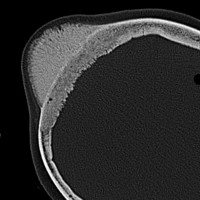

骨内髄膜腫 osseous meningioma

骨内増殖をする髄膜腫です。頭蓋骨腫瘍と間違えるようなものです。触った感じは骨腫ですが,CTでは,表面が毛羽立っていて,頭蓋冠に浸潤していることが特徴です。浅側頭動脈からの豊富な血流があります。

わずかですが頭蓋内にも腫瘍があり,硬膜が肥厚してガドリニウム増強されます。

頭蓋骨をかなり広範におかすので骨は捨てません。開頭して取り外した骨の厚くなっている部分と髄膜腫で軟らかくなっている部分を削除して,それから骨片をオートクレーブで短時間熱処理して,元あった所にもどします。下の画像は手術後1年半が経過したものですが,髄膜腫の再発はなく,熱処理骨弁は吸収されないで生着しています。